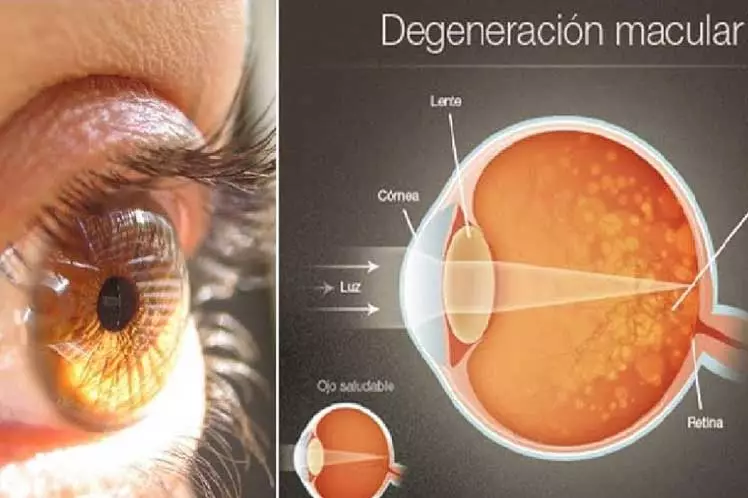

Degeneración macular: Cuida tu salud visual

Degeneración macular: Detéctala a tiempo

Degeneración macular seca: ¿Qué es y cómo tratarla?